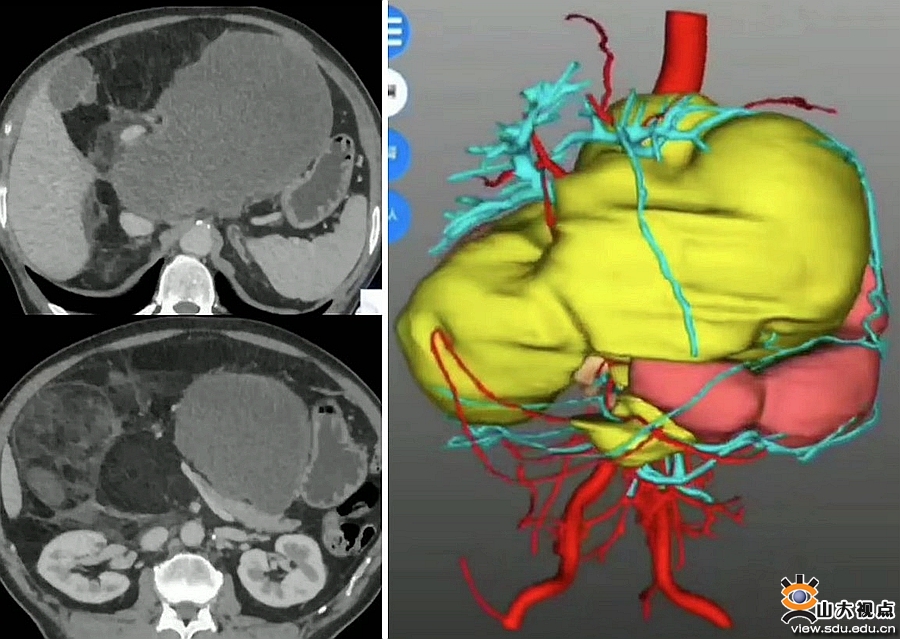

患者是一位中年男性,因腹胀喘憋就诊,检查后发现腹腔巨大肿瘤,因肿瘤侵犯多脏器、重要血管,辗转多家省市级医院后均被拒绝手术。患者抱有一线希望来到齐鲁医院就诊,李峰接诊后详细了解病情,结合外院穿刺病理脂肪肉瘤,考虑肿瘤有分段切除可能。术前,李峰团队与麻醉科、重症医学科等科室进行了充分沟通。术中,见巨大肿瘤几乎占据上腹部,完全包绕左右肝动脉、肝固有动脉、门静脉、左右肝管、胆总管、胰头、胃窦、右肾周脂肪囊、结肠系膜等,采取逐一击破策略,成功实施“腹膜后肿瘤切除+左、右肝动脉分别部分切除、端端吻合+胰十二指肠切除(其中左、右肝管分别胆肠吻合)+右半结肠切除+右肾周脂肪囊切除+右肾上腺切除术”。

手术历时12余小时,在普通外科副主任王磊教授指导下,在麻醉科赵连英,手术室护士刘俊英、张彤,团队陈述海、郑阳等通力协作下,患者术后恢复比预期顺利,肝功能良好,术后CTA显示肝动脉、门静脉等血管通畅。患者术后恢复良好,17天出院。